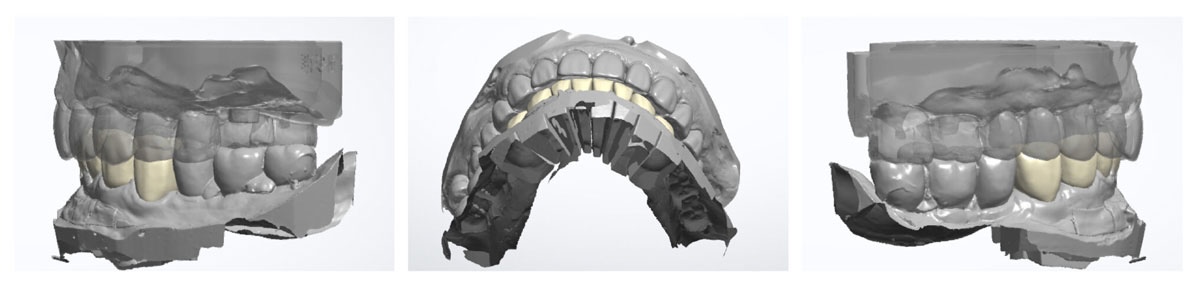

數位掃描模擬

蒔美不只專注於牙齒本身,更注重整體笑容,利用Rayface臉部掃描和DSD數位微笑設計,來模擬笑容改變後的效果,並與醫師共同討論最適合的全瓷假牙設計。